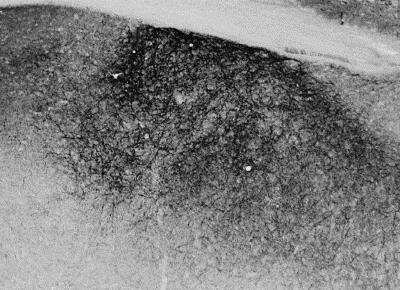

Immunohistochemistry-Frozen: Proenkephalin Antibody [NBP1-20963] - Staining of PFA-perfused cryosection of Rat Striatum. HRP-staining with Ni-DAB after Biotin-SP-anti-goat amplification. Data obtained by Prof. Erik Hrabovszky, Inst, Exp, Med., Budapest, Hungary.

Immunohistochemistry-Frozen: Proenkephalin Antibody [NBP1-20963] - Staining of PFA-perfused cryosection of Mouse Stria terminalis. HRP-staining with Ni-DAB after Biotin-SP-anti-goat amplification. Data obtained by Prof. Erik Hrabovszky, Inst, Exp, Med., Budapest, Hungary.

WB: Preliminary experiments gave an approx. 40 kDa band in rat brain lysates after 0.2 ug/ml antibody staining. Please note that currently we cannot find an explanation in the literature for the band we observe given the calculated size of 30.8 kDa band according to mouse NP_001002927.1 and 30.9 kDa band according to rat NP_058835.1. The 40 kDa band was successfully blocked by incubation with the immunizing peptide. IHC-Fr: Rat brain (striatum) shows staining of dense enkephalinergic axon plexus. Mouse brain (stria terminalis) shows staining of a dense enkephalinergic fibre network in the bed nucleus.